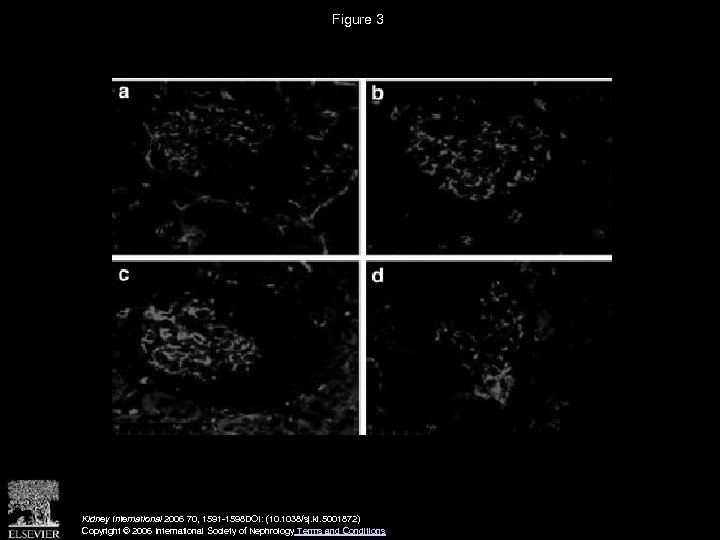

Figure 3 Kidney International 2006 70, 1591 -1598 DOI: (10. 1038/sj. ki. 5001872) Copyright © 2006 International Society of Nephrology Terms and Conditions